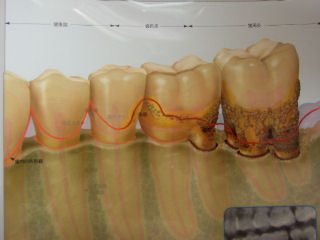

歯の周りにはこのように、歯周ポケットという “ ポケット ”があります。

いわゆるポケットです。

歯周病菌で骨が溶かされると、この歯周ポケットは深くなります。

深くなったポケットは、いっぱい食べかすを溜め込みます。

溜め込んだ食べかすは、細菌の餌になりどんどん毒素を出していきます。

綺麗にシャンプー(歯磨き)をして、汚れを綺麗に落としてからリンス(デンタルリンス)をしましょうね。

そうすると効果が期待できますよ。